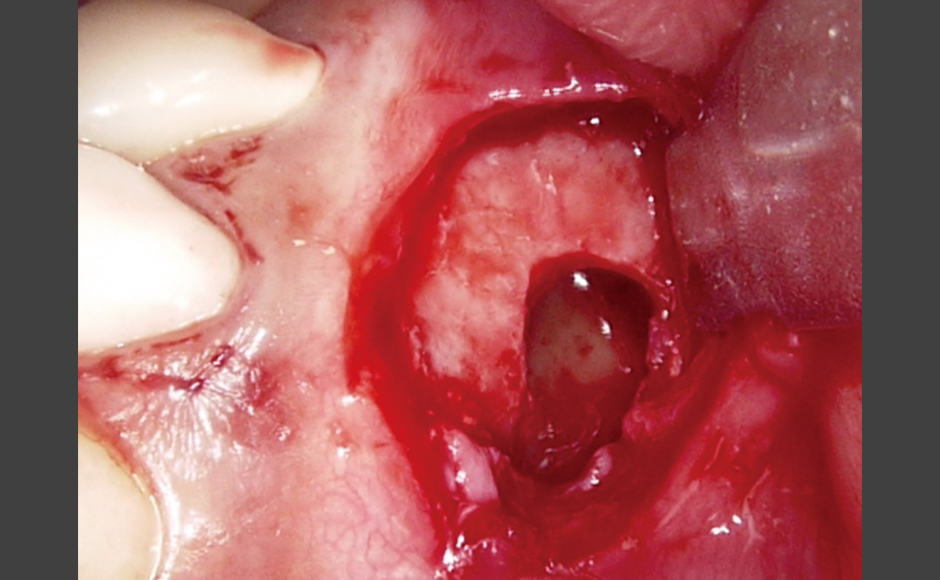

レーザーの応用による効果的な根管治療 症例1:多数歯に対してのレーザー使用 症例2:歯根嚢胞に対し外科的処置とレーザー併用